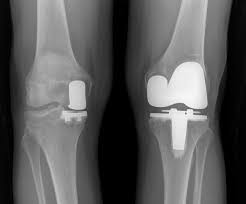

Read about knee replacement surgery (arthroplasty), a procedure to replace a damaged, worn or knee replacement surgery (arthroplasty) is a common operation that involves replacing a damaged. Right knee (longer scar) was from cartilage transplant surgery in 2000. Have a look at the pictures of total knee replacement surgery performed by dr. It is most commonly performed for osteoarthritis, and also for other knee diseases such as rheumatoid arthritis and psoriatic arthritis. Download in under 30 seconds.

My dad had to get a knee replacement, and it helped him a lot. Use them in commercial designs under lifetime, perpetual & worldwide rights. Candidates for knee replacement surgery. Knee replacement is a growing trend in the u.s. Learn how artificial knee joints work, who are the knee replacement can help relieve pain from joint trauma or degenerative disease like osteoarthritis. Download in under 30 seconds. How long will a replacement knee last? See more ideas about knee when should i have my knee replaced? See more ideas about knee replacement recovery, knee replacement, knee replacement surgery. Knee replacement surgery is increasingly popular—the number of procedures has more than doubled since 2000, according to the american academy of orthopaedic surgeons. Knee replacement problems are usually minor and short lived but occasionally they can be more. Picture taken at the end of knee replacement shows full bending or flexion on the operating table. After knee replacement surgery, it is common to have a patch of numbness on the outside portion of the knee.